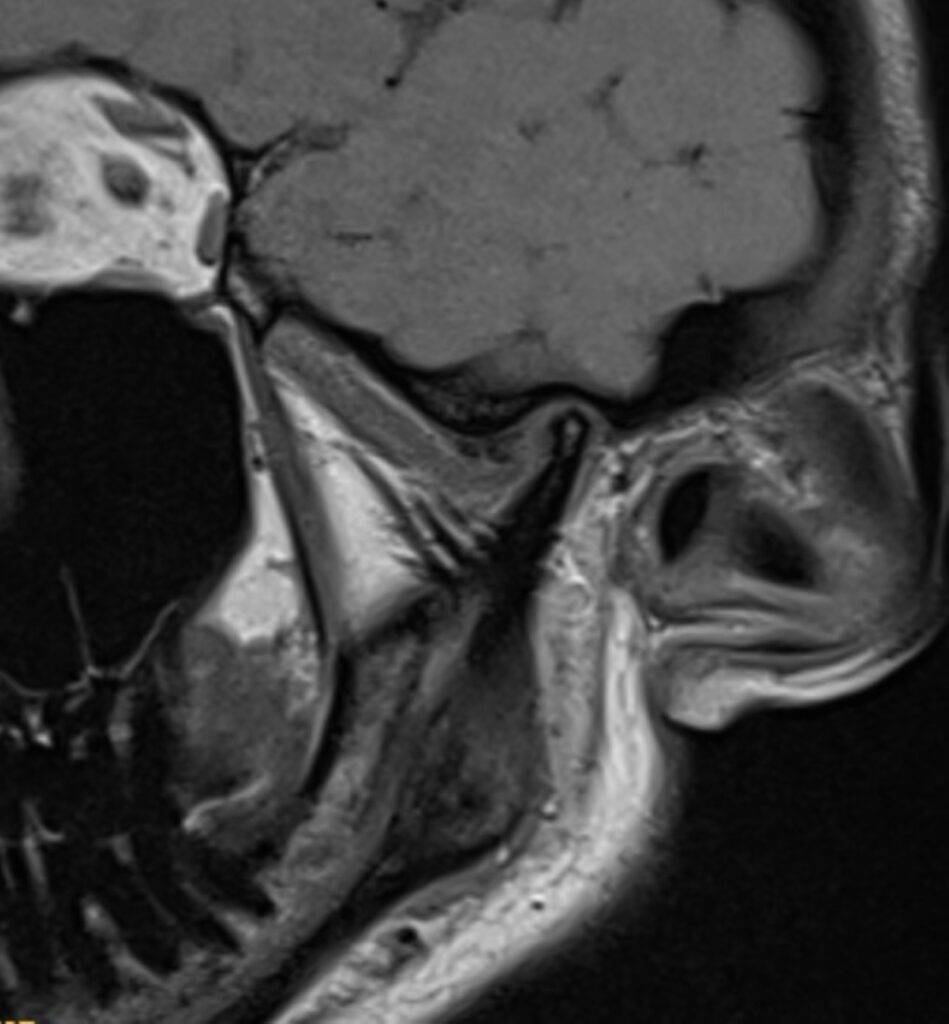

Eine Magnetresonanztomographie des Kopfes, kurz die MRT Kopf genannt, ist ein medizinisch bildgebendes Verfahren. Die MRT Kopf Untersuchung stellt mit Hilfe von Magnetfeldern und Radiowellen insbesondere unser Gehirn, Ohr, Nase und Nasennebenhöhlen, Augen, Kiefer, sowie genaue Strukturen detailliert dar. Vor allem bei diffusen oder langanhaltenden Kopfschmerzen kann eine MRT aufschlussreich sein. Vor allem ermöglicht eine Kopf MRT Einblicke in verschiedene neurologische Erkrankungen.

Eine Kopf MRT liefert Ärzte und Radiologen detaillierte Bilder. Zu sehen sind das Gehirn, Schädelknochen, Blutgefäße und anderer umgebende Gewebe im Kopfbereich.

- Tumore und Zysten: Die MRT Kopf kann sowohl gutartige als auch bösartige Tumore im Gehirn erkennen. Sie kann auch bei der Identifizierung von Zysten und anderen strukturellen Anomalien helfen.